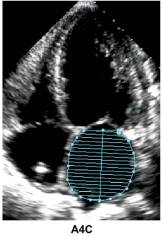

3、HFpEF—左室收缩功能评估

注:LVEDVI (LV end-diastolic volume index) ,左心室舒张末容积指数;

LVESVI ( LV end-systolic volume index),左心室收缩末容积指数.

4、左室收缩功能指标的正常值范围